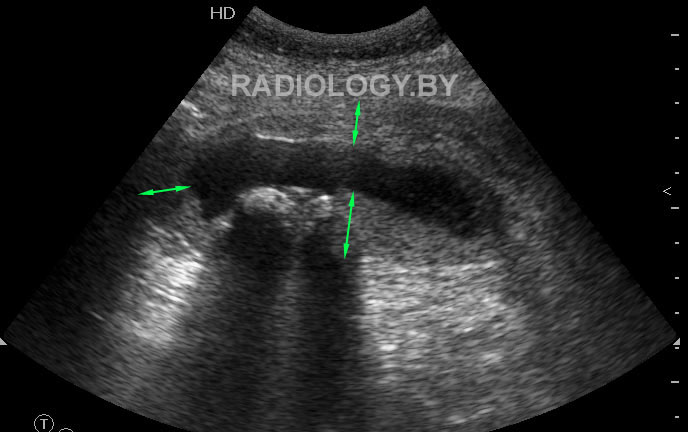

Женщина средних лет с болями в правом подреберье поступила в приемный покой хирургической клиники.

Выявлены следующие изменения желчного пузыря

Ваше заключение? Оцените примерную толщину стенки желчного пузыря.

Acute cholecystitis; sludge, gall stones. Predicted wall thickness about 8-12 mm.